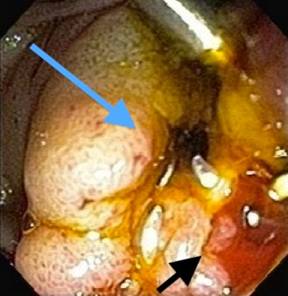

The patient was a high surgical risk subject due to recent angina/cardiac ischemia and an endoscopic attempt at hemostasis was pursued. Repeat ERCP revealed yellow bile at the common bile duct/sphincterotomy site and active red blood flowing from the pancreatic duct orifice (Figure 1). Pancreatogram revealed a dilated duct (6 mm) at the head of the pancreas, without any contrast extravasation or evidence of aneurysmal dilatation. The ampulla/proximal portion of the pancreatic duct was injected with epinephrine. Four plastic pigtail stents were deployed into the pancreatic duct (5Fr x 9 mm; 5Fr x 5 mm; 5Fr x 3 mm (n=2)) in an effort to tamponade the source of bleeding. Two resolution clips were also deployed at the pancreatic duct orifice, adjacent to the stents (Figure 2). No evidence of bleeding was seen at the completion of the procedure.

Figure 1. Common bile duct orifice at the ampulla showing yellow bile (blue arrow) and pancreatic duct orifice showing red blood (black arrow). |